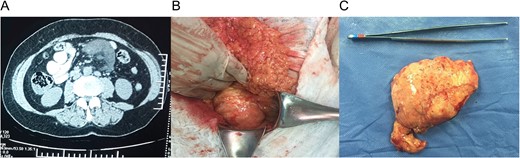

She had normal blood work, and a contrast-enhanced abdominal computed tomography (CT) revealed a 9 × 7 × 4 cm3 mass within the small bowel mesentery near the root of the mesentery with several lymph nodes surrounding it. No other lesion or masses were found (Fig. 1A).

(A) Computed tomography (CT) with a 9 × 7 × 4 cm mass within the small bowel mesentery near the root of the mesentery. (B) Mass in the root of small bowel mesentery near the mesenteric vessels. (C) External surface of the mass.